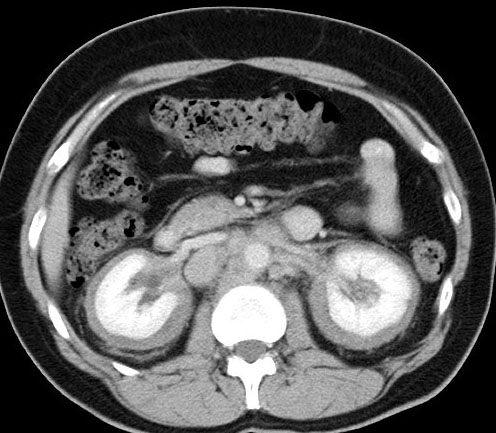

CASO 1: Paciente de 58 años que se realiza TC de abdomen tras historia de dolor abdominal y hematuria microscópica. Refiere pérdida de peso en las últimas semanas.

Estamos ante una afectación bilateral del espacio perirrenal, más evidente en el lado derecho, por masas de densidad de partes blandas en un paciente con numerosas adenopatías retroperitoneales. Estaría indicado realizar una biopsia, ya que el diagnóstico principal orienta hacia un síndrome linfoproliferativo, espcialmente linfoma no Hodgkin tipo B.

2. LINFOMA.

El linfoma renal presenta una gran variedad de manifestaciones. Entre un 3 y un 8 % de linfomas estudiados por TAC tienen afectación renal o perirrenal, más frecuentemente el tipo no Hodgkin.

Patrones de afectación del linfoma renal:

- Multiples masas renales en el riñón (+frecuente)

- Lesión solitaria.

- Adenopatías retroperitoneales con extensión directa a riñón y EPR (nuestro caso de hoy).

- Afectación del espacio perirrenal aislada.

- Infiltración difusa de uno o ambos riñones.

En el caso de que el linfoma afecte al EPR, se ve como una masa homogénea que ocupa este espacio y que desplaza el riñón hacia adelante, ocupando a menudo también el espacio pararrenal anterior. La afectación aislada del EPR por el linfoma es poco frecuente (<10%), es más común la extensión directa desde las adenopatías o grandes conglomerados/masas retroperitoneales (+frec) o la extensión desde el riñón.